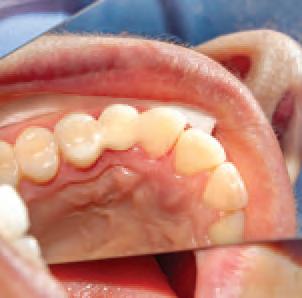

Another significant danger area arises in relation to case assessment. If the clinician’s grasp of the clinical situation is not accurate, this will undermine the prospect of a successful outcome, and create both clinical and dentolegal risk. Insufficient attention to pre-operative case assessment and treatment planning can lead to difficulties, which a more careful approach could have avoided. A robust pre-op assessment helps to ensure that there is a clearer understanding of the clinical picture, including possible complications, and will put the clinician in a position to more accurately judge if the treatment is within their competence and experience before proceeding. It is important that the patient’s expectations are realistic and aligned with the clinical findings and potential treatment outcomes. Sometimes it may be necessary to reconsider and revise treatment plans, e.g., in light of a tooth becoming non-vital, is it still suitable as a bridge abutment or does the plan need re-evaluation? Common failings seen in claims include: 4 failure to adequately assess and advise on the condition of teeth preoperatively; 4 inadequate investigations/special tests/diagnostics; 4 using and relying upon inappropriate radiographs for assessment; 4 failure to identify the most appropriate approach to address clinical presentation; 4 periodontal condition not recorded; 4 failure to stabilise dentition before proceeding with complex treatment; and, 4 failure to assess abutment teeth radiographically, periodontally, etc.